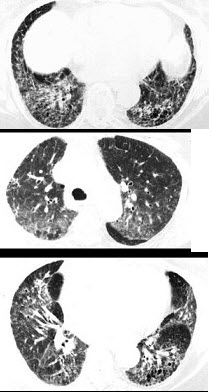

间质性肺炎的患者疾病在发作的时候,其临床症状有很多,但由于间质性肺炎的一些症状不是特别明显,因此,常常会被忽视,专家说间质性肺炎发生的病因主要是细菌、病因,那么下面我们介绍的是间质性肺炎的症状表现。专家为我们介绍说,我们所说的间质性肺炎,还叫做是叫间质性肺疾病或者是弥漫性肺疾病等,顾名思义它是肺间质的病变。间质性肺炎不是一个单一的疾病,而是一大类疾病的总称,约有百余种,已知一小部分病因已明,如尘肺、饕物性肺炎、放射性肺炎等;但有相当一部分病因不明,如特发性肺纤维化、结节病等。那么间质性肺炎症状主要有什么呢?专家称,间质性肺炎的症状主要是以下的几个方面: